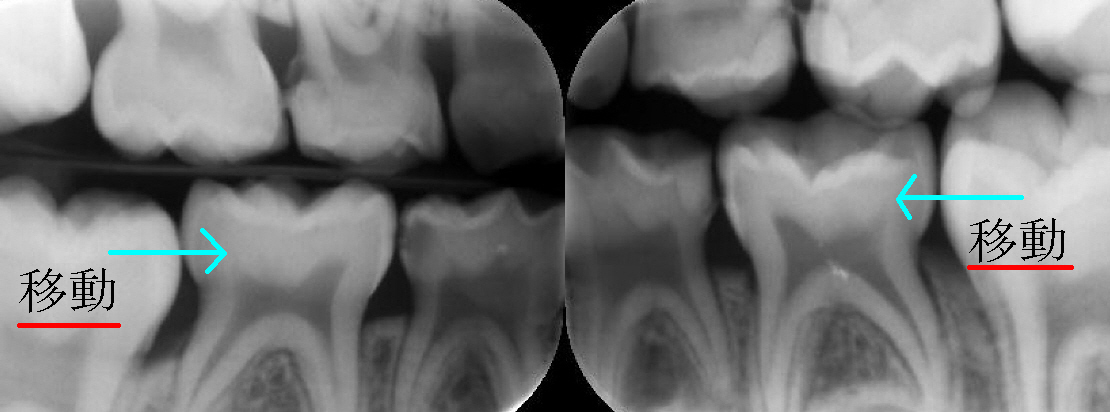

甘食(ソフトキャンディ―、飴、ソフトドリンク等)をお口にされる頻度の多いお子様は、乳歯の奥歯に虫歯が

できます。 あせい歯科では4歳ぐらいになればたいてい左のような写真を取ります。 これでお口の中をみるだけでは分からない虫歯が写ります。